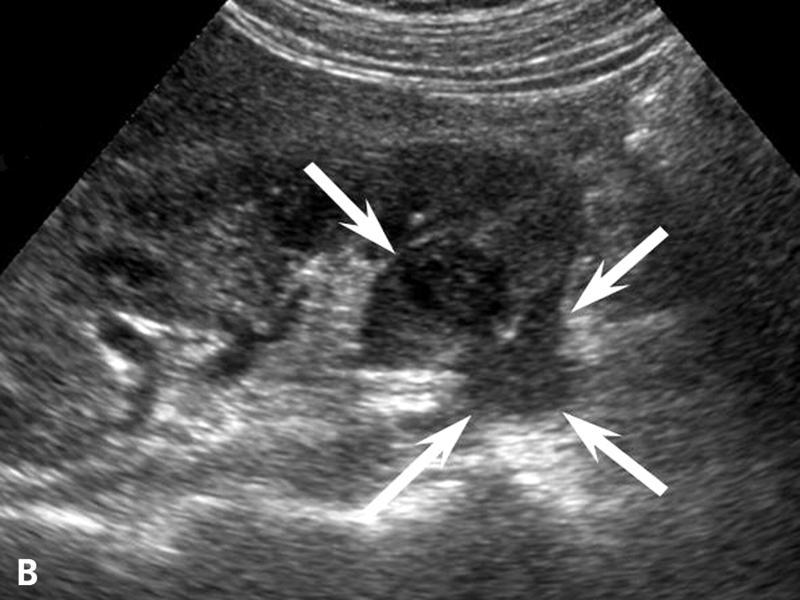

Pancreatic Psydocyst

Spherical fluid collection of pancreatic enzymes that arise from inflamatory, necrotic and hemorrhage processes of the pancrreas

persistently elevated amylase and lipase

Pancreatic Psydocyst

Spherical fluid collection of pancreatic enzymes that arise from inflamatory, necrotic and hemorrhage processes of the pancrreas

persistently elevated amylase and lipase

Pancreatic Psydocyst

Spherical fluid collection of pancreatic enzymes that arise from inflamatory, necrotic and hemorrhage processes of the pancrreas